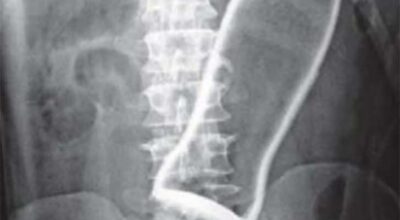

Esta recopilación de imágenes recoge alguna de las situaciones más estrambóticas que se han podido dar en una sala de rayos X. Todas ellas tienen algo en común: Son objetos extraños para el cuerpo humano que, de alguna manera han encontrado una vía de entrada, pero se han perdido a la hora de encontrar la de salida.

Muñecas de juguete descabezadas, botellas, armas, frascos, botes de plástico, teléfonos y hasta una cinta de casete pueden encontrarse en esa suerte de “punto limpio” al que ha quedado reducido el interior de los afectados.